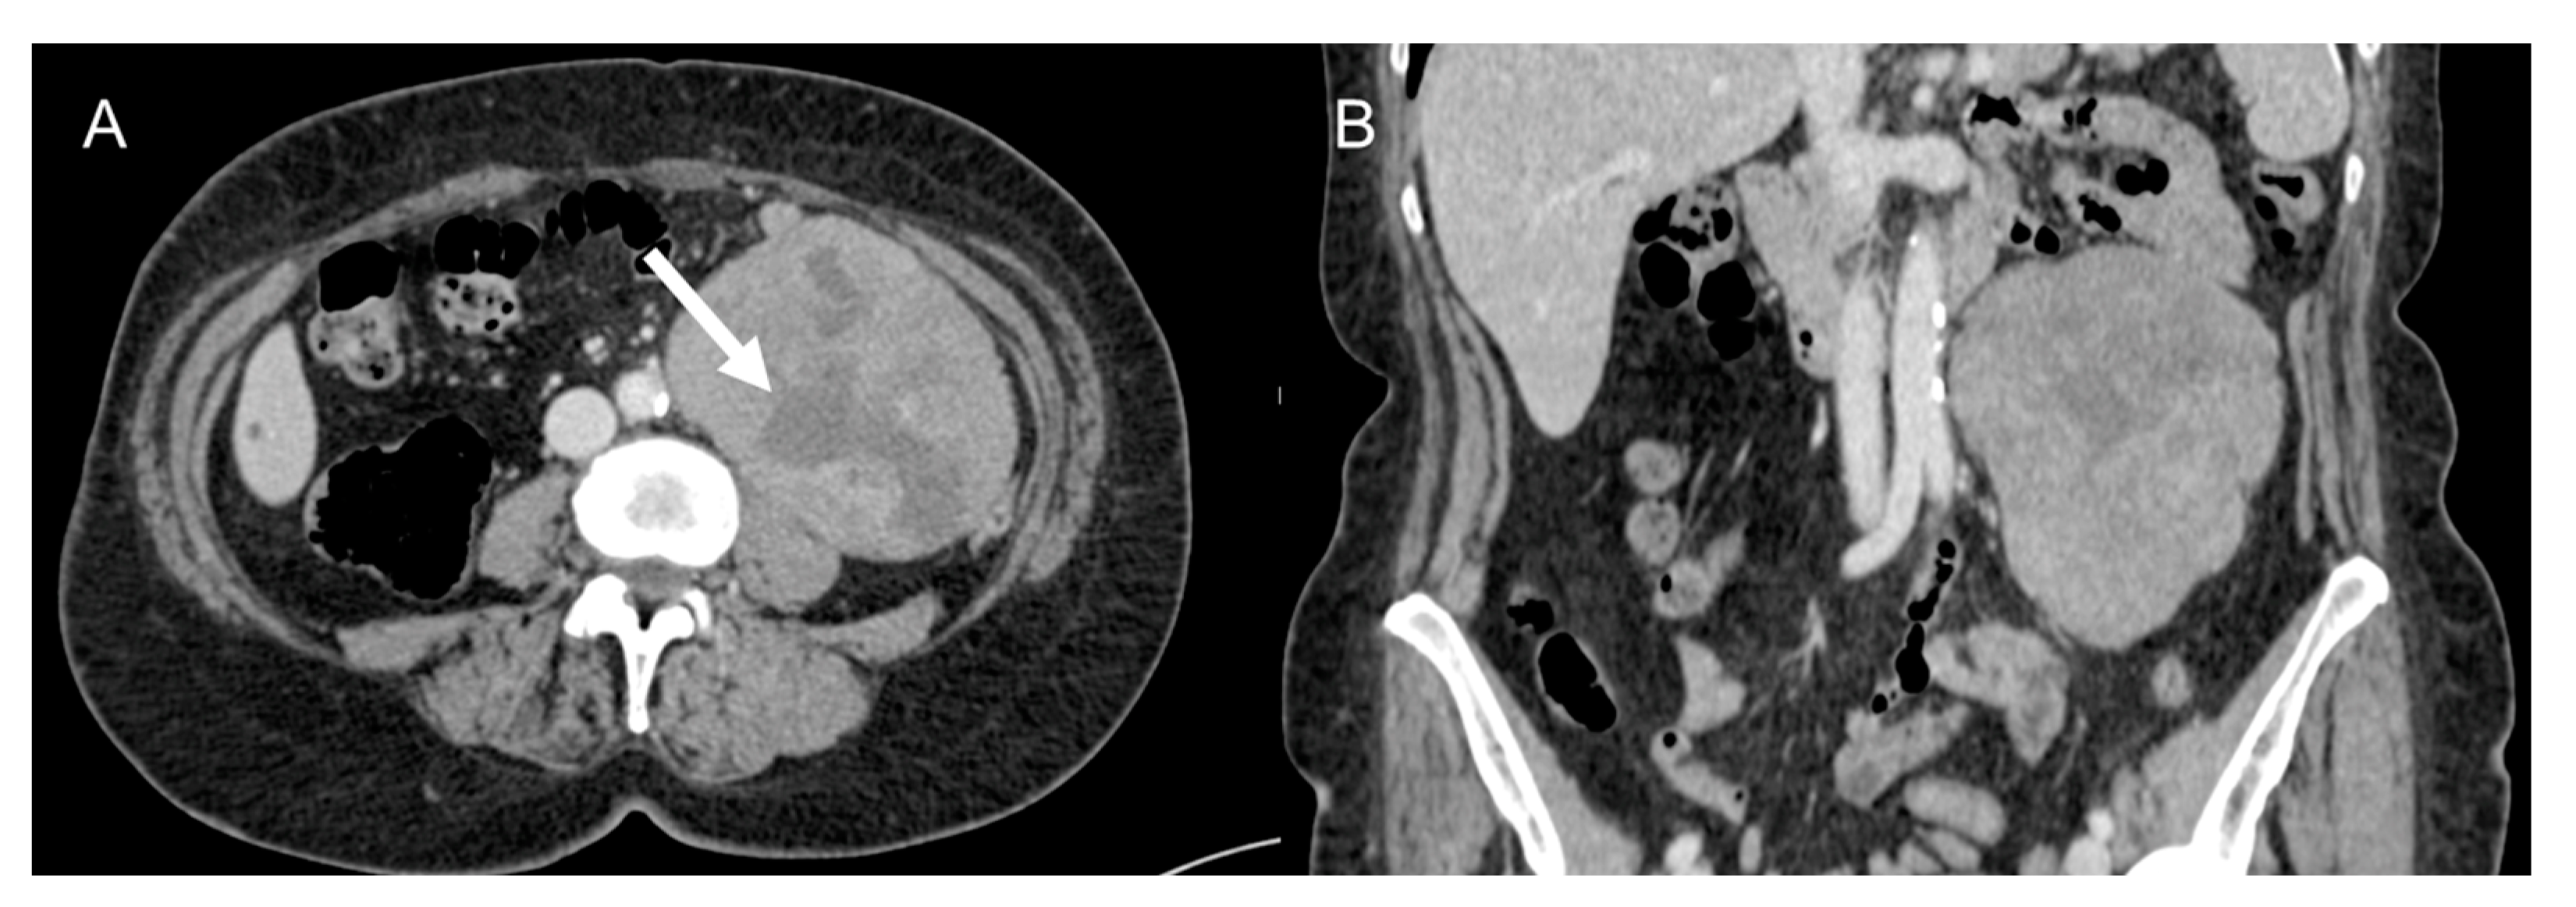

LMS is a smooth muscle tumor [38], more common than LPS in younger age groups [6]. Its most frequent location is the retroperitoneum, near the inferior vena cava [43]. LMS are heterogeneous masses (Figure 4), with irregular peripheral enhancement and enhancing solid portions, mixed with cystic, hemorrhagic, or necrotic areas. LMS show marked T2 hypointensity on MRI and are similar in attenuation to uterine myometrial smooth muscle on CT [39]. Fatty components and calcifications are usually absent [34,38]. The evidence of a large, heterogeneously enhancing, necrotic retroperitoneal mass contiguous with a vessel, with extra- and intraluminal involvement, is highly suggestive of LMS [12,37,43]. It could stem from the inferior vena cava, extending into the intrahepatic portal veins or superior mesenteric vein, or even from small vessels such as renal or gonadic veins. Differentiation from extrinsic compression can be challenging [12,40].

Figure 4.

Retroperitoneal leiomyosarcoma in a 63-year-old woman. Axial (A) and coronal (B) CT images on venous phase show a 10.2 cm heterogeneous mass with central area of low attenuation consistent with necrosis (arrow).